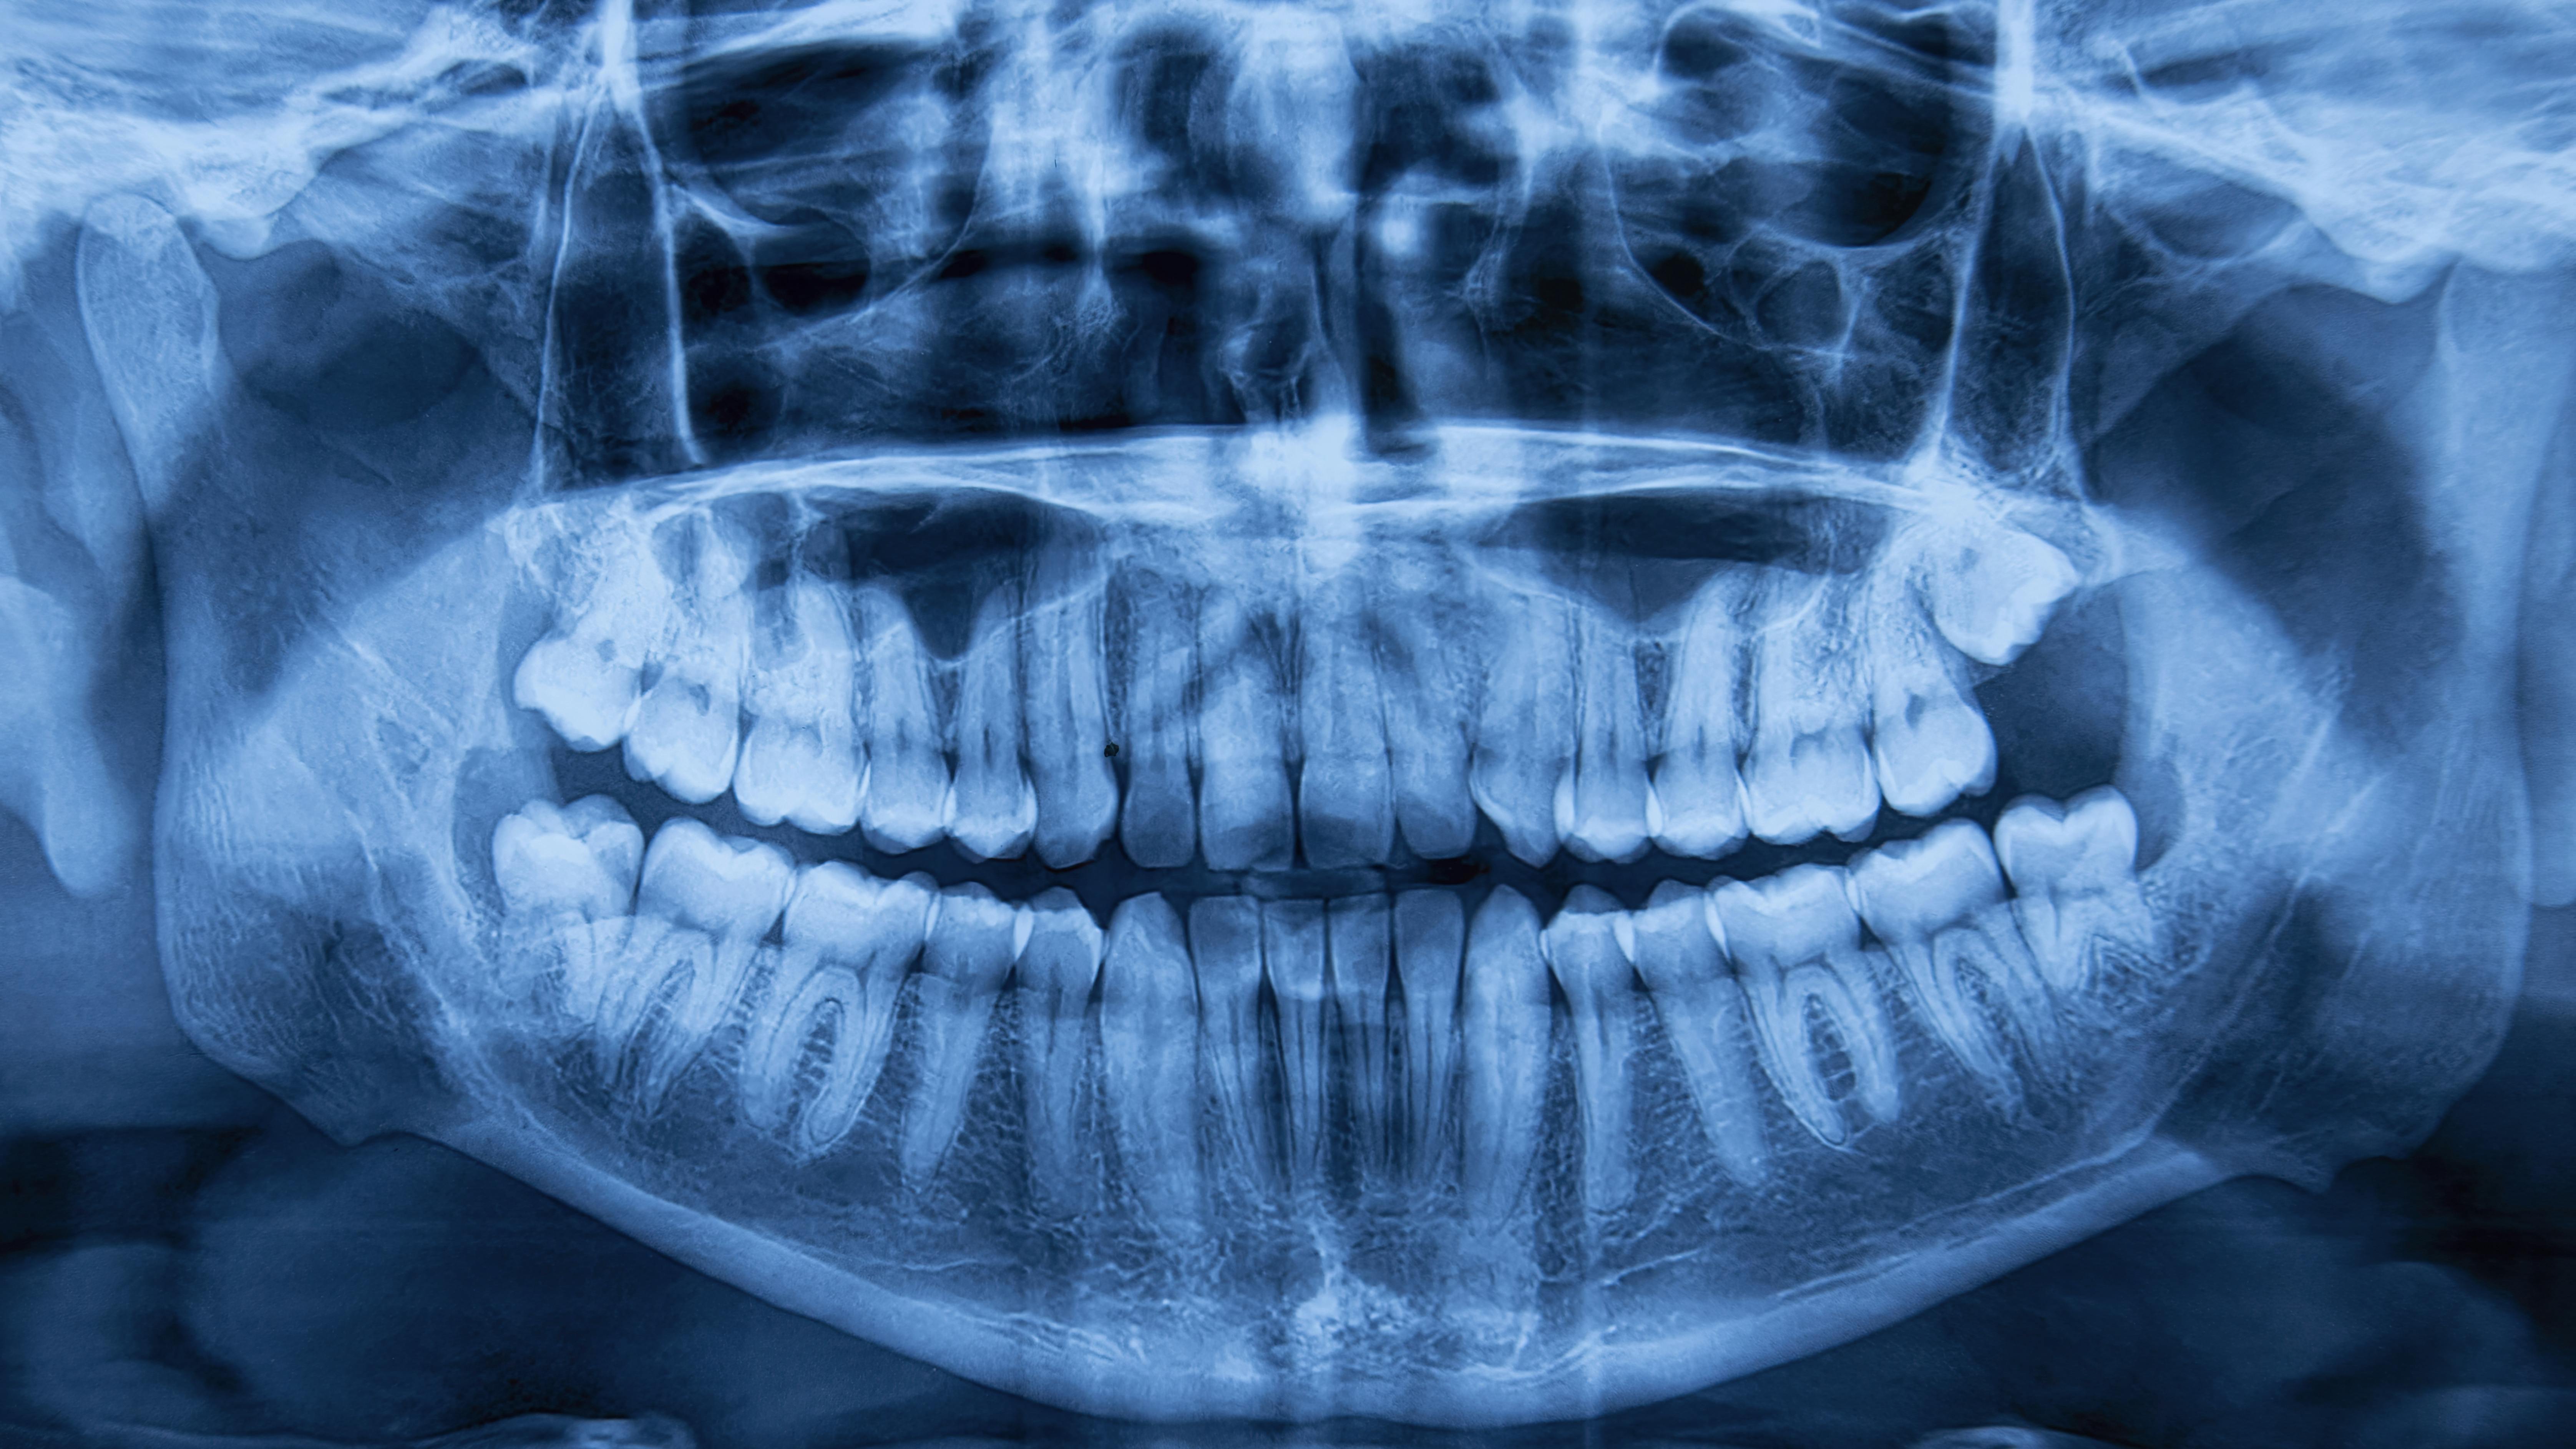

- High-quality radiographs are vital for accurate diagnosis, treatment planning, and patient trust, especially in complex cases like implants and endodontics.

Diagnostic-quality imaging is the starting point for accurate treatment planning. Whether evaluating bone levels for implants or identifying endodontic pathology, poor radiographs result in missed or incorrect diagnoses, which ultimately impact both clinical outcomes and patient trust.

Implant placement and bone density assessment

Pulp vitality and endodontic working length evaluation

Restoration margin analysis

Early pathology identification

Periodontal disease progression tracking